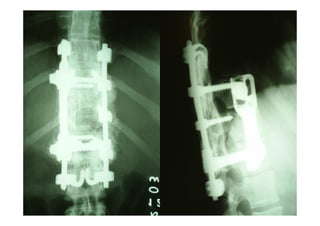

FRATURAS

Tratamento:

- Fixador externo

- Definitivo:

- Redução extemporânea + gesso

- Redução cruenta + osteossíntese

figura